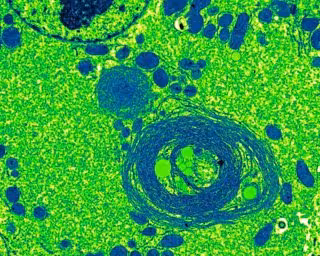

Este estudio demuestra que el proceso de reciclaje de componentes celulares que se encuentra activo en las células sanas y que es conocido como autofagia, "previene la acumulación de una proteína involucrada en el crecimiento del tumor".

Los efectos que los científicos detectaron al bloquear la autofagia en los hígados de ratones resultaron "muy similares" a aquellos que se observan en pacientes humanos con la enfermedad de hígado graso no alcohólico (NASH), una patología crónica que incrementa el riesgo de desarrollar cáncer de hígado.

Estos efectos se deben a la acumulación de la proteína Yes-associated ('Yap'), que, tal y como demuestra la investigación, "promueve cambios en el comportamiento de las células del hígado incrementando el riesgo de padecer cáncer".